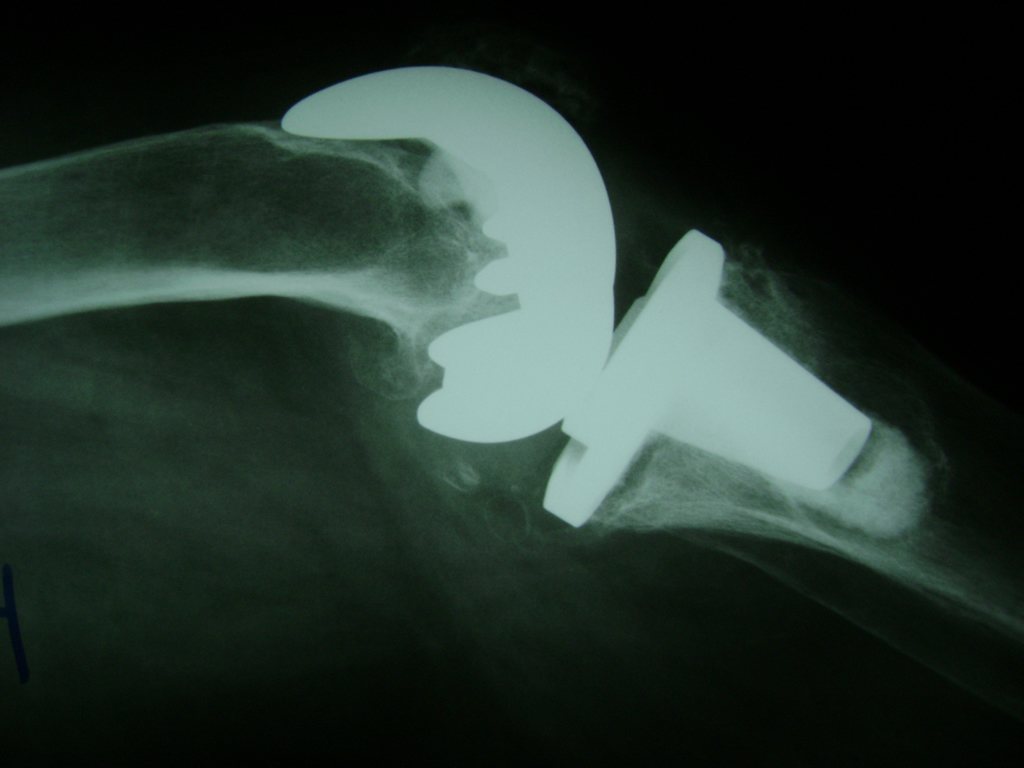

Cirugías de Codo - Rodilla

La artroscopia de rodilla es un cirugía en el cual la estructura interna de la articulación es examinada ya sea para realizar un diagnostico o para realizar un tratamiento, este procedimiento se realiza utilizando un instrumento parecido a un pequeño tubo llamado artroscopio.